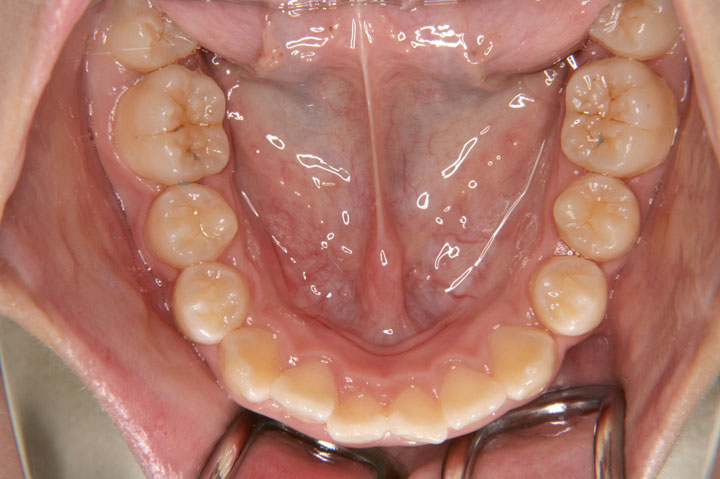

上顎前歯のデコボコを主訴に来院された小学校6年生の女子です。前期治療としてリンガルアーチを用いた上顎前歯の被蓋改善とヘッドギアーによる上顎大臼歯の遠心移動を行いました。その後、非抜歯でエッジワイズ装置(デーモンシステム)を用いて後期治療を行っております。